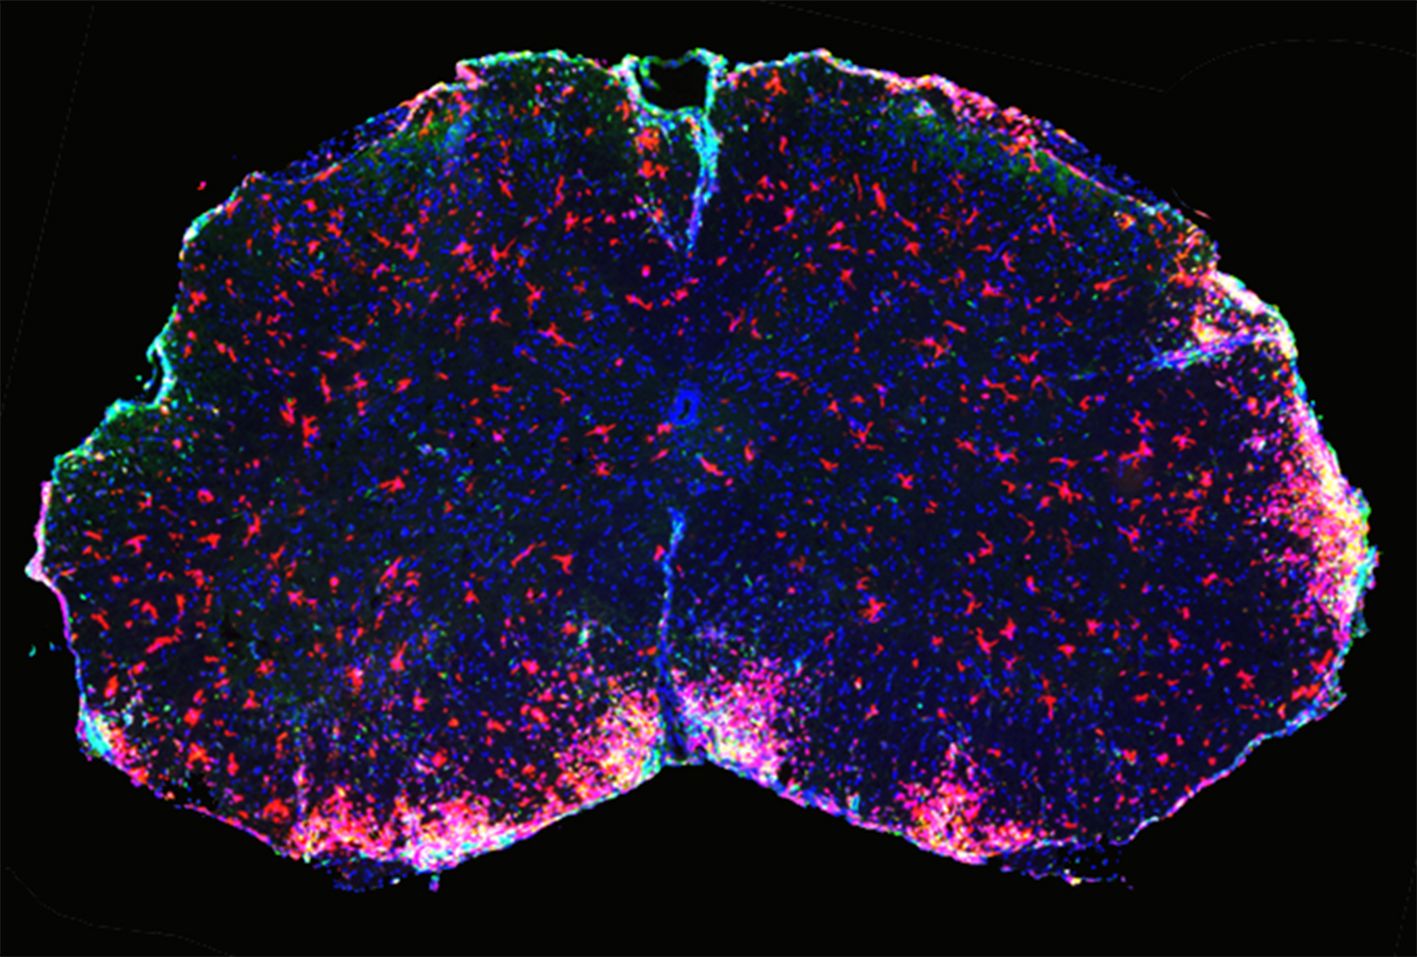

Bei HCA2 handelt es sich um einen sogenannten G-Protein-gekoppelten Rezeptor, der unter anderem auf einem bestimmten Typ weißer Blutkörperchen vorkommt, den neutrophilen Granulozyten. „Bei Tieren, die mit DMF behandelt wurden, waren viel weniger Granulozyten in das Nervensystem eingewandert als bei unbehandelten Tieren. Bei den Tieren, denen der HCA2-Rezeptor fehlte, blieb die Zahl der eingewanderten Granulozyten trotz Behandlung mit DMF unverändert hoch“, sagte Schwaninger.

In weiteren Experimenten an Zellkulturen fanden die Wissenschaftler heraus, dass die Aktivierung des HCA2-Rezeptors für die Einwanderung der weißen Blutkörperchen in das zentrale Nervensystem verantwortlich ist. DMF blockiert diese Einwanderung und verhindert so die Entzündung. „Mit unserer Studie konnten wir erstmals zeigen, dass die Schutzwirkung von DMF auf dem HCA2-Rezeptor beruht. Wir schließen aber nicht aus, dass es noch weitere Mechanismen gibt“, stellte Wettschureck fest.